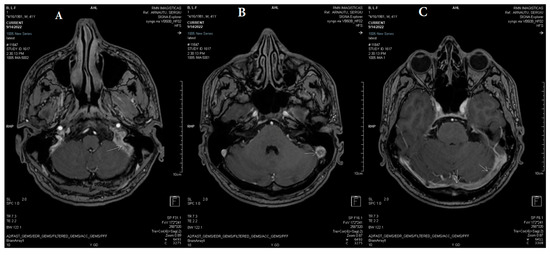

2.2. Neuroimaging Data